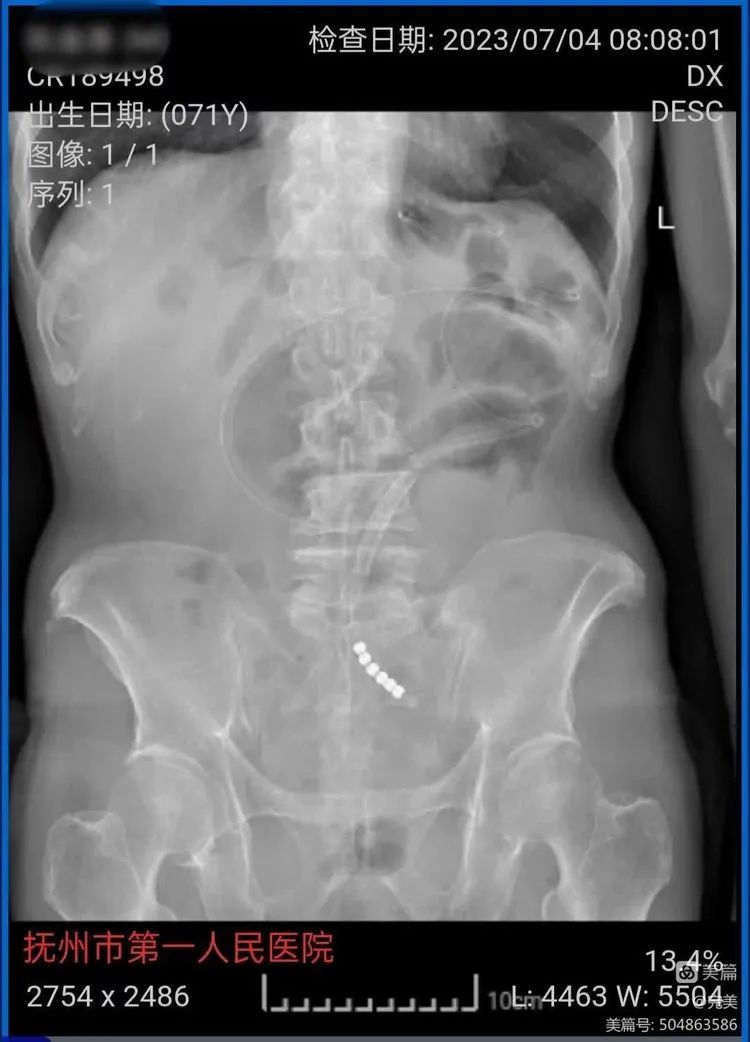

考虑到患者既往已行一次大手术,传统胃管引流时间长,效果欠佳,所以决定行DSA引导下小肠减压引流管置入方式进行小肠深部引流。转入我科后立即给予治疗。半小时后,只见一股黄色液体喷涌而出,陆续达1000多ml,躺在治疗床上的阮大伯神志清楚,立即说道:“医生,我感觉肚子不胀了,舒服多了!”可见治疗效果立竿见影。

管道的材质是硅橡胶,比较柔韧,治疗时医生在DSA引导下将导管通过鼻腔注入小肠,实现肠梗阻的引流和减压,导管全长约3m,特别适合治疗低位不完全性肠梗阻,腹部手术引起的肠粘连。